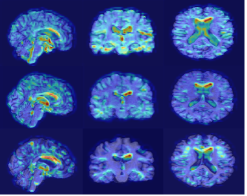

Refer to caption

(a) Original sMRI

(b) MixStyle

(c) EM1

(d) EM2

AIBL

(e) Original sMRI

(f) MixStyle

(g) EM1

(h) EM2

OASIS

(i) Original sMRI

(j) MixStyle

(k) EM1

(l) EM2

Figure 3: Grad-CAM visualizations on 3D sMRI samples across cohorts. The figure presents NC, MCI and AD subjects from ADNI (top row), AIBL (middle row), and OASIS (bottom row). For each cohort, columns show: original sMRI scans, MixStyle baseline, EM1 based on mean, standard deviation, and skewness, and EM2 extending EM1 with kurtosis.

Grad-CAM visualizations in Fig. 3 show that, compared to MixStyle, the proposed EM variants produce more stable and focused activations within cortical and subcortical regions commonly affected by AD. EM1 provides the clearest localization, reducing noisy responses outside brain tissue and highlighting disease-relevant areas more consistently. EM2 shows a similar trend, though its attention maps are slightly more diffuse. These improvements are most evident in ADNI and AIBL, while OASIS shows smaller but consistent gains. Overall, incorporating higher-order moments encourages the model to focus on more anatomically meaningful structures.